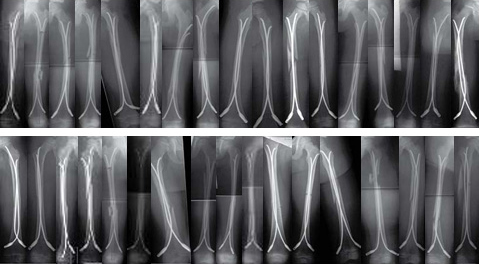

Case of a 8-year old boy with a closed lower leg fracture after football game.

Case 2